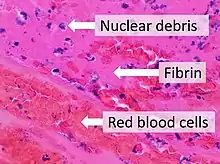

Fibrin (also called Factor Ia) is a fibrous, non-globular protein involved in the clotting of blood. It is formed by the action of the protease thrombin on fibrinogen, which causes it to polymerize. The polymerized fibrin, together with platelets, forms a hemostatic plug or clot over a wound site.

When the lining of a blood vessel is broken, platelets are attracted, forming a platelet plug. These platelets have thrombin receptors on their surfaces that bind serum thrombin molecules,[1] which in turn convert soluble fibrinogen in the serum into fibrin at the wound site. Fibrin forms long strands of tough insoluble protein that are bound to the platelets. Factor XIII completes the cross-linking of fibrin so that it hardens and contracts. The cross-linked fibrin forms a mesh atop the platelet plug that completes the clot. Fibrin was discovered[2] by Marcello Malpighi in 1666.[3]

Excessive generation of fibrin due to activation of the coagulation cascade leads to thrombosis, the blockage of a vessel by an agglutination of red blood cells, platelets, polymerized fibrin and other components. Ineffective generation or premature lysis of fibrin increases the likelihood of a hemorrhage.